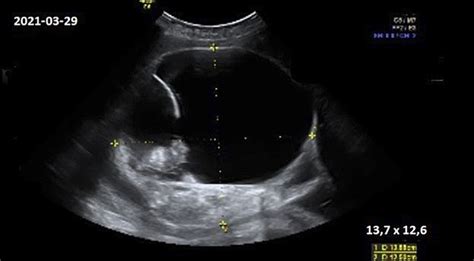

- Ultragarsinis tyrimas: Šis tyrimas yra vienas svarbiausių. Jis gali būti atliekamas transvaginaliai (su zondų, įvedamu į makštį). Ultragarsas padeda nustatyti, ar persileidimas jau įvyko, ar vaisius dar gyvas. Jei persileidimas įvyko, ultragarsas gali parodyti, ar vaisius ir placenta buvo visiškai pašalinti iš gimdos. Esant praleistam persileidimui, ultragarsas parodys, kad vaisius negyvas, tačiau vis dar yra gimdoje.